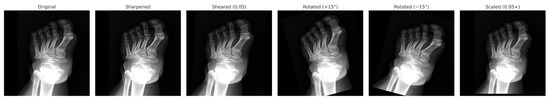

Deep Learning for Sex Estimation from Whole-Foot X-Rays: Benchmarking CNNs for Rapid Forensic Identification

Diagnostics 2025, 15(22), 2923; https://doi.org/10.3390/diagnostics15222923 - 19 Nov 2025

Background: Accurate sex estimation is crucial in forensic identification when DNA analysis is impractical or remains are fragmented. Traditional anthropometric approaches often rely on single bone measurements and yield moderate levels of accuracy. Objective: This study aimed to evaluate deep convolutional neural networks (CNNs) for automated sex estimation using entire foot radiographs, an approach rarely explored. Methods: Digital foot radiographs from 471 adults (238 men, 233 women, aged 18–65 years) without deformities or prior surgery were retrospectively collected at a single tertiary center. Six CNN architectures (AlexNet, ResNet-18, ResNet-50, ShuffleNet, GoogleNet, and InceptionV3) were trained using transfer learning (70/15/15 train–validation–test split, data augmentation). The model performance was assessed using accuracy, sensitivity, specificity, precision, and F1-score. Results: InceptionV3 achieved the highest accuracy (97.1%), surpassing previously reported methods (typically 72–89%), with balanced sensitivity (97.5%) and specificity (96.8%). ResNet-50 followed closely (95.7%), whereas simpler networks, such as AlexNet, underperformed (90%). Conclusions: Deep learning applied to whole-foot radiographs delivers state-of-the-art accuracy for sex estimation, enabling rapid, reproducible, and cost-effective forensic identification when DNA analysis is delayed or unavailable, such as in mass disasters or clinical emergency settings. Full article